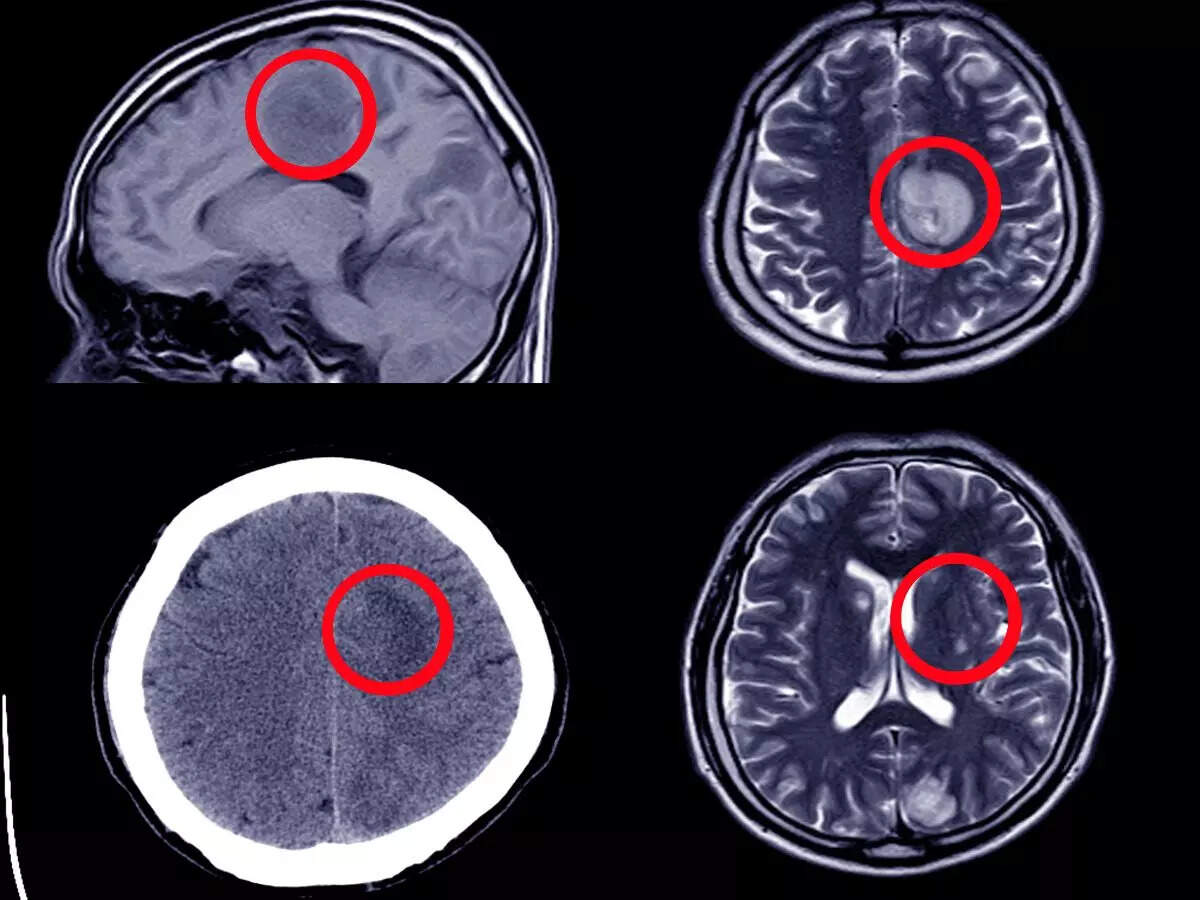

Cerebral Aneurysm Angiogram

Cerebral aneurysm, CT scan Stock Image M136/0212 Science Photo Signs Brain Aneurysm It may also be called an intracranial aneurysm or. A brain aneurysm, or cerebral aneurysm, is a bulge that develops in the weakened wall of an artery within the brain. This bulge or 'bubble' can fill. A brain aneurysm is a deformity of an artery where a spot in the arterial wall in the brain bulges and fills with blood.. Signs Brain Aneurysm.